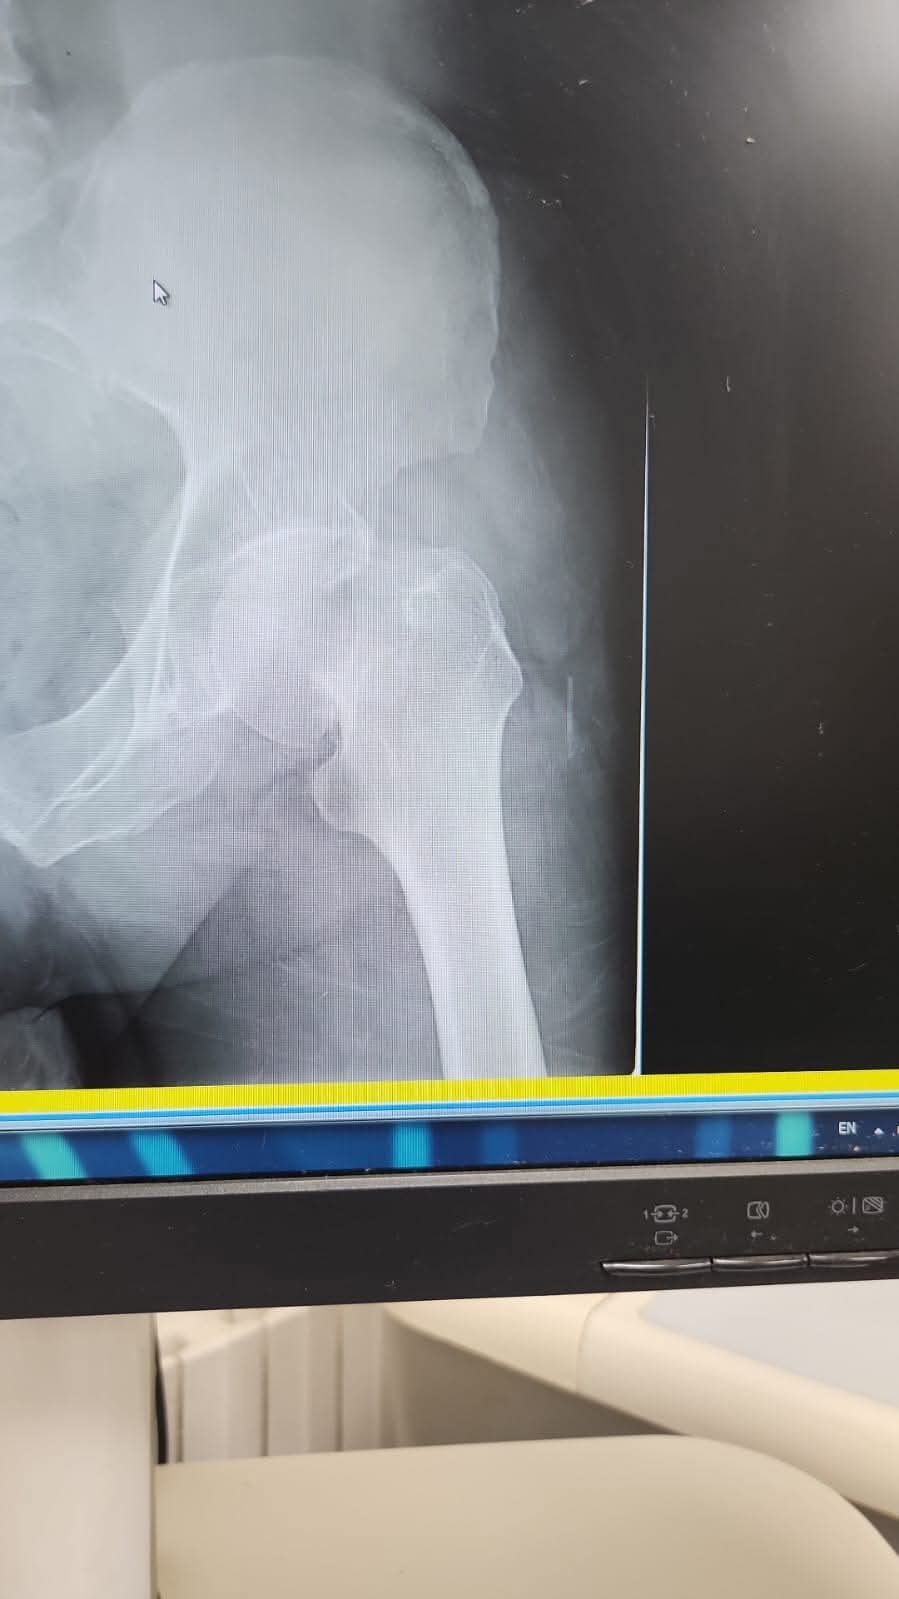

وطنا اليوم -  يقوم بعمليات تثبيت الكسور المعقدة بشكل طاريء وتبديل المفاصل بشكل مبرمج  مما خفف على المواطنين البحث عن أسرة في مستشفيات مركزية رغم صعوبة عمليات العظام من الناحية التقنية في المستشفيات النائية  إضافة الى  استقبال اعداد كبيرة بالعيادات ومعالجة جميع المرضى بالطرق المثلى انه الدكتور الانسان البارع والمتميز يزيد البريزات طبيب العظام في مستشفى الاميرة سلمى / ذيبان عيادة العظام  علماً بأنه كان  مستشفى تحويلي منذ تاسيسه والدكتور البربزات وقبل اربع سنوات في عام 2020  منذ انتقاله للمستشفى يقوم بهذه العمليات ومن بينها  عمليات نوعية لمرضى يعانون من كسور معقدة في الترقوة واجراء عمليات دقيقة ومعقدة لكسور لمرضى في مختلف أنحاء الجسم وعمليات تثبيت الكسور المعقدة وتركيب المفاصل وغيرها الكثير  والديسك " وآلامه وتبعاته وعلاجه وإجراء عمليات معقده وصعبه.

وأجرى الدكتور البريزات عمليات كبرى في جراحة العظام والتي تحتاج إلى مراكز متقدمة ومتطورة. وكذلك العمل على تثبيت أغلب انواع الكسور بطريقة طارئة وتبديل المفاصل بطريقة مبرمجة بما يتناسب مع امكانات المستشفى والتي هي  جزء من  العمليات الدورية بمستشفى الاميرة سلمى في ذيبان  والتي تخفف العبئ على المستشفيات المركزية وعلى المواطن في آن واحد.